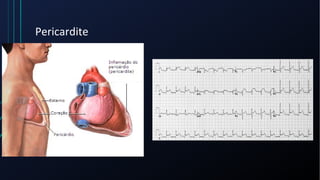

Dor torácica pode ter diversas causas, incluindo cardíacas como síndrome coronariana aguda, dissecção de aorta e pericardite, e não cardíacas como problemas pulmonares, musculoesqueléticos e do trato gastrointestinal. É importante avaliar a história clínica, características da dor e exame físico para identificar a possível causa e orientar o tratamento adequado.